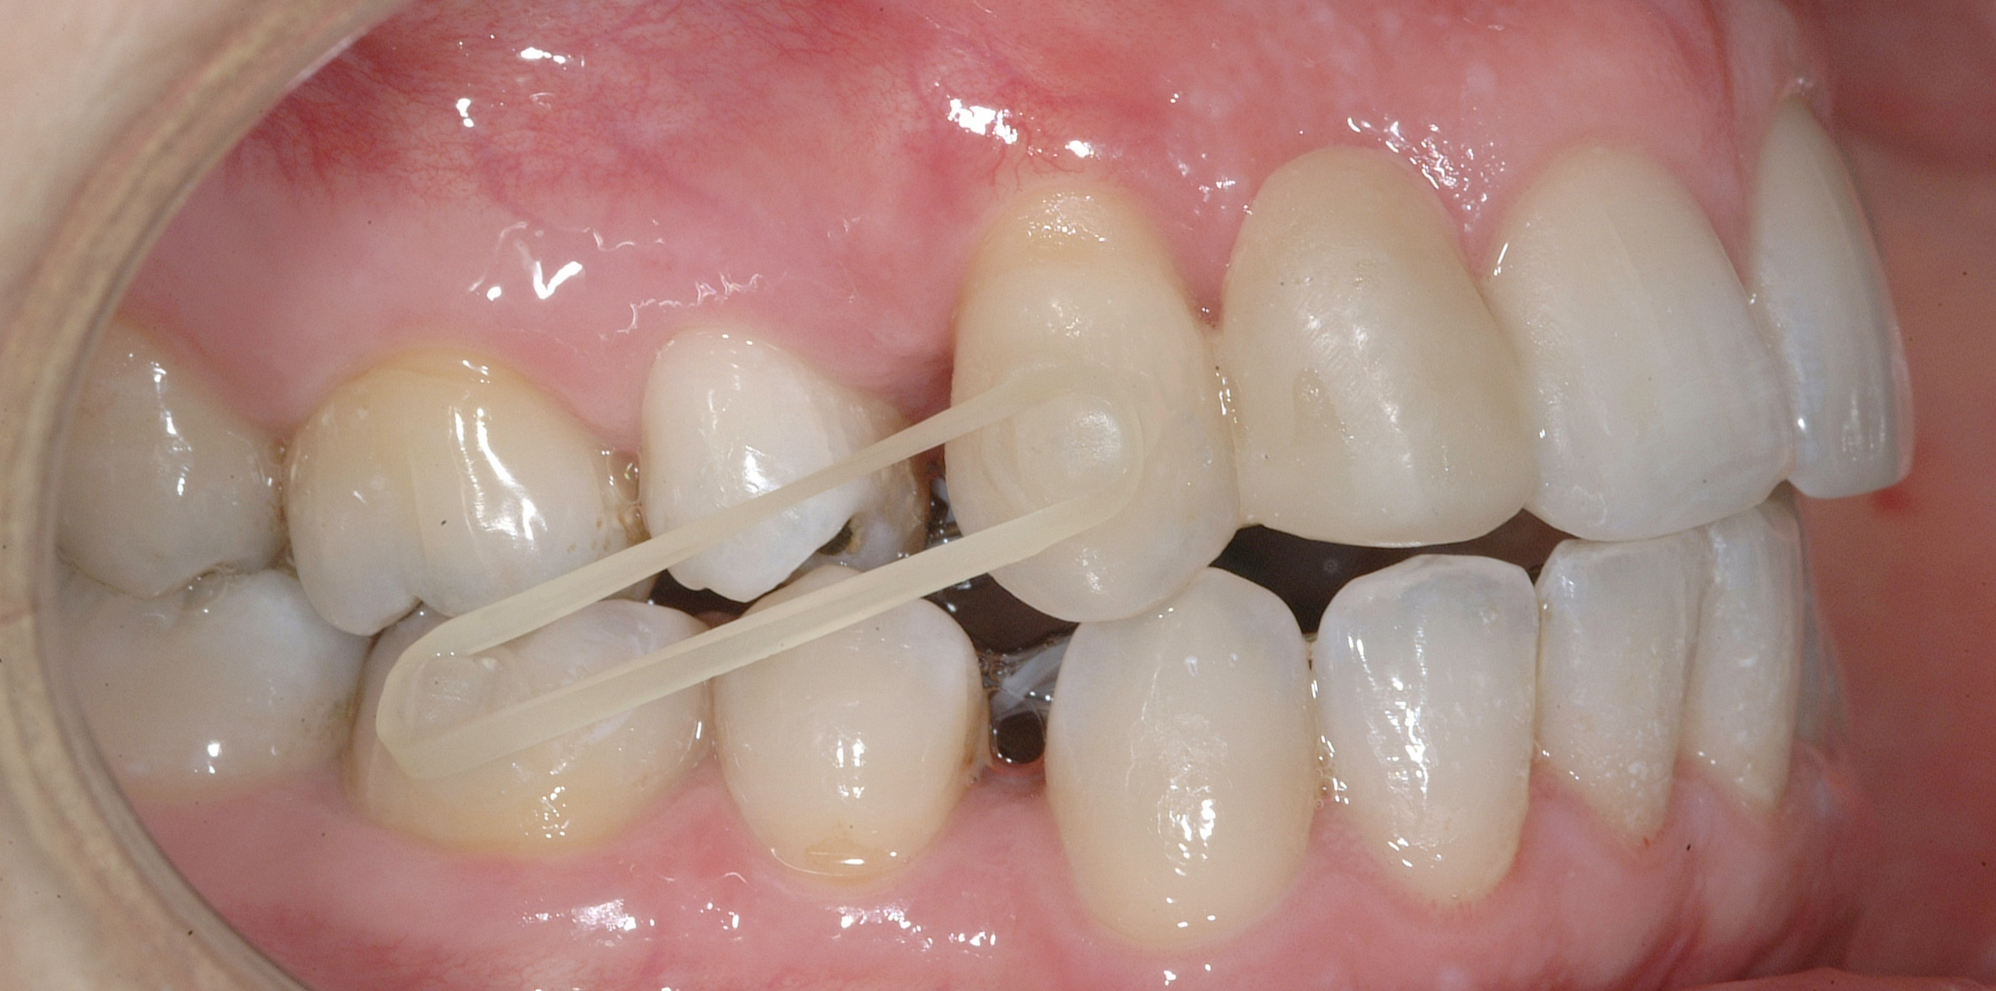

In seguito, è stato modellato e applicato con tecnica adesiva diretta un pontic estetico in resina composita in sede 1.2, bondato sia distalmente a 1.1 sia mesialmente a 1.3, per un movimento en-masse in ancoraggio medio del gruppo frontale superiore, ottenuto nel settore 1 mediante forza elastica singola su arco .016” acciaio.

Per completare la chiusura degli spazi inferiori in ancoraggio medio è stata applicata una catenella elastica leggera da 3 a 6 ed elastici di Classe II (3/16 da 4.5 once) bilaterali e domiciliari-notturni, applicati vestibolarmente su bottoni estetici bondati su 3.6, 4.6, 1.3 e 2.4 (Figure 7a-e).

La rifinitura del caso ha previsto il completamento del livellamento del piano occlusale posteriore inferiore mediante meccanica cross-over con sezionali in acciaio .017”x .025” applicati sui primi e secondi molari e catenelle di derotazione tra i centrali superiori e tra 1.6 e 1.5 (Figure 8a-b).